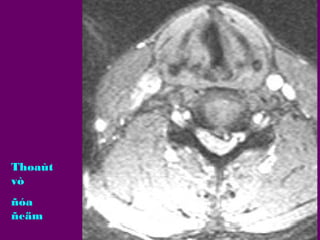

Thoaùt

vò

ñóa

ñeäm